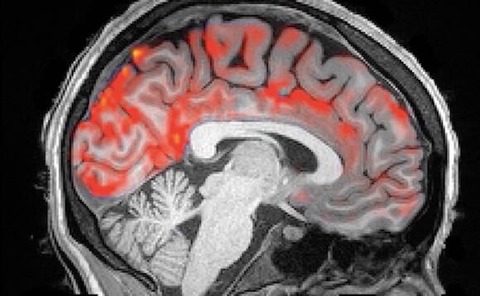

この度アメリカ・ボストン大学の研究グループは、睡眠中、脳内で脳脊髄液が毒素の清掃を行っている様子がわかるMRI映像を公開した。

マウスを対象とした動物実験によって、脳が働く過程で蓄積されてしまう毒素が睡眠で物理的に洗い流されることなら既に知られていた。『Science』(11月1日付)に掲載された今回の研究は、このことが人間にも当てはまるのかどうかを確認したものだ。

それを知るために、生物医学エンジニアのローラ・ルイス氏は、大勢の参加者にMRIの中で眠ってもらうように頼んで、そのときの脳の様子を観察するという実験を行った。

その結果、ノンレム睡眠になると、脳脊髄液の大きくゆっくりとした波が、脳全体を洗い流していることが明らかになったのである。

さらに脳波図からは、ノンレム睡眠に入ると神経細胞が同期して、スイッチのオンオフが始まることも判明した。

神経細胞が一斉に発火しなくなるので、それらはあまり酸素を必要としなくなる。このために脳への血流が減少する。

そうしてできた隙間の中に脳脊髄液が勢いよく流れ込んでくるのだ。

要するに、比喩でもなんでもなく、脳脊髄液が昼の間にたまった毒物を本当にじゃぶじゃぶと洗い流しているのである。